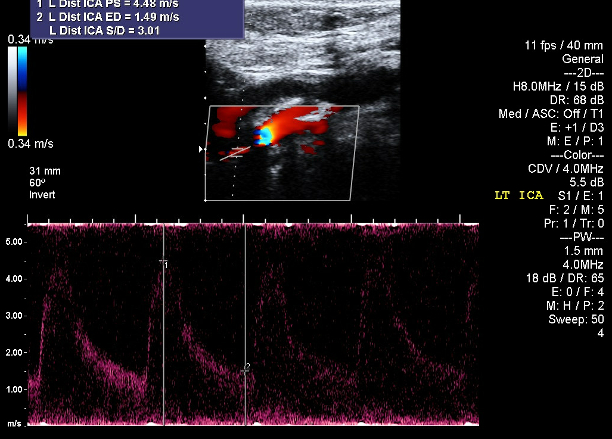

An 80-year-old woman with well-controlled hypertension presented with new-onset labile systolic pressures ranging from 90 to 200 mmHg. At age 63, she received radiation for SCC of the tongue. Eight years later, she developed episodic headaches and paresthesias during hypertensive spikes. Cardiology workup revealed persistent BP variability (see Figure 1), inappropriate heart rate responses, and sensitivity to antihypertensives—leading to hypotensive episodes. Carotid angiography showed 85% stenosis of the right ICA, successfully stented. A decade later, she had significant left-sided carotid disease (Figures 2a and 2b). Despite interventions, she continued to have erratic BP fluctuations and recurrent syncopal episodes. Radiation-induced baroreflex failure was suspected based on her clinical course and history.